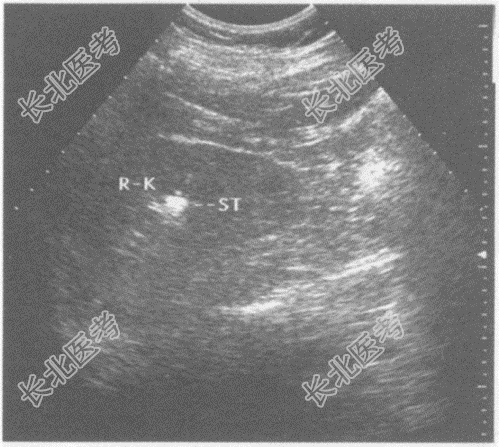

- 单项选择题临床资料:女, 33岁,自述右侧腰部不适。

临床物理检查: 右肾区叩痛。

超声综合描述:右肾下极集合系统内可见强回声光团, 后伴弱声影。

超声提示: A、右肾错构瘤

B、右肾尿酸盐结晶沉积

C、右肾结石

D、右肾钙乳症

E、右肾多发囊肿